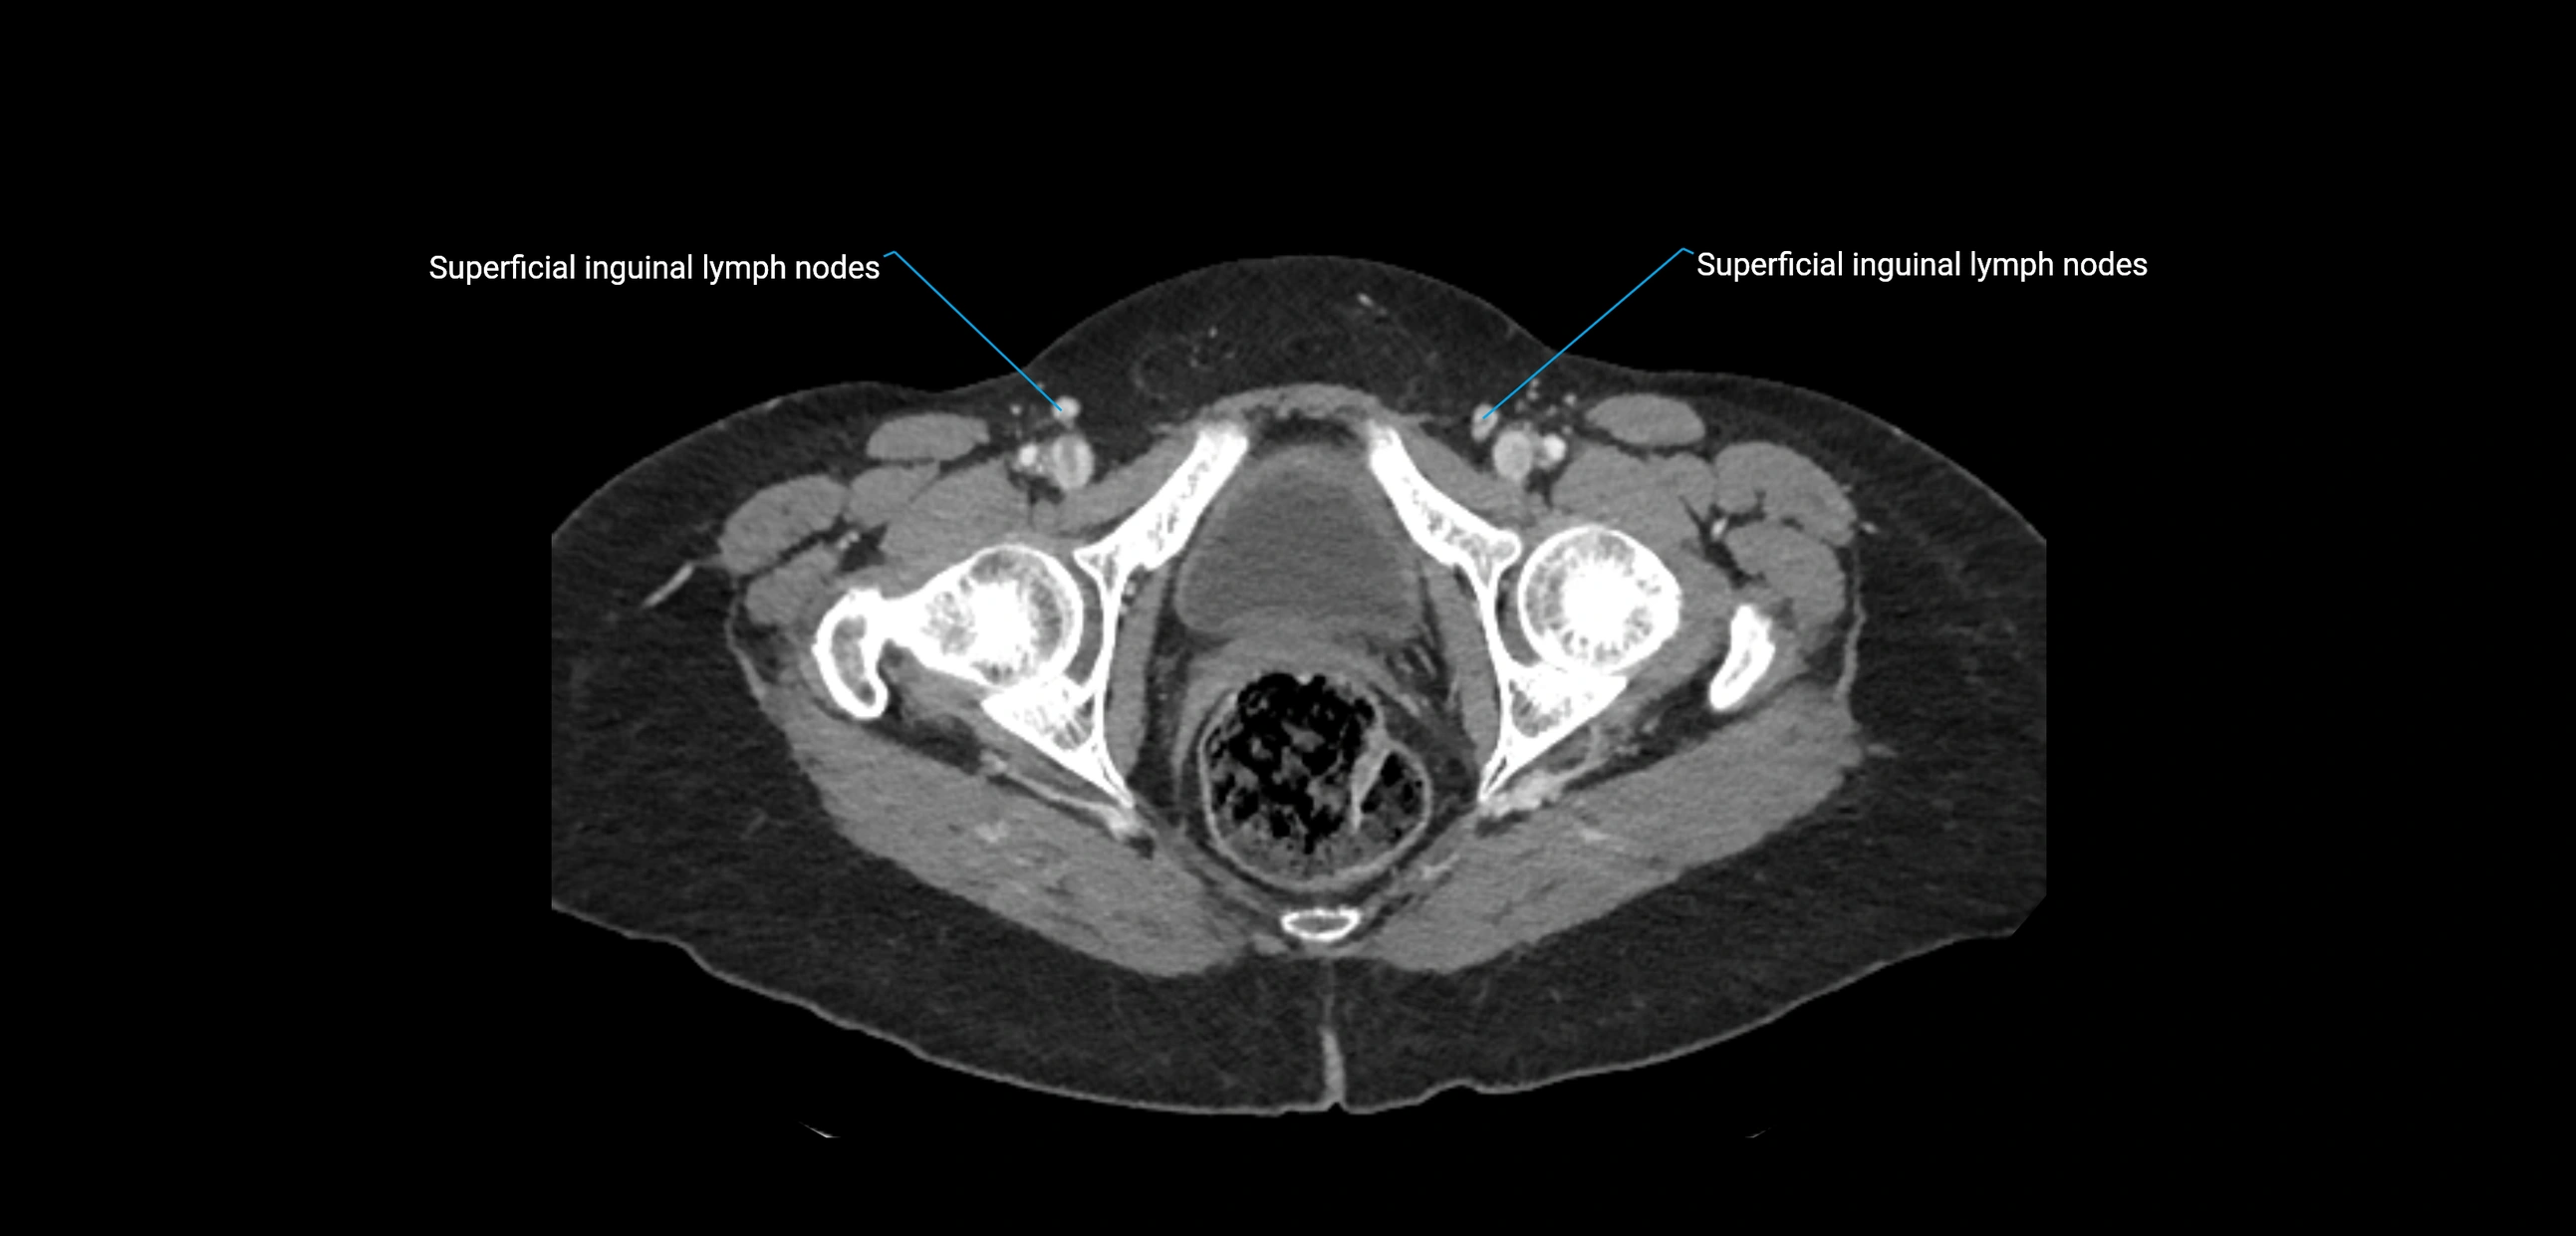

CT Appearance

CT Pre-Contrast:

• Nodes appear as soft-tissue density nodules adjacent to the aorta and IVC

• Calcification may be seen in chronic infections (e.g., tuberculosis)

CT Post-Contrast:

• Normal nodes enhance homogeneously

• Malignant nodes may show heterogeneous enhancement, central necrosis, or conglomerate formation

• Size >1 cm short axis is suspicious, though morphology and distribution are equally important